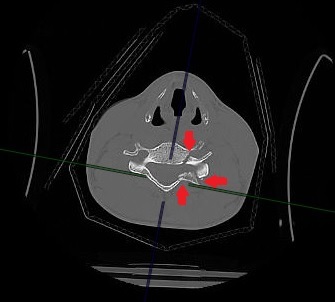

Проведенное обследование с помощью УЗИ, томографии всего тела и МРТ выявило множественные переломы шейных позвонков, вывих одного из них, разрыв межпозвонкового диска с образованием грыжи, сдавившей спинной мозг. По словам врача-нейрохирурга, кандидата медицинских наук Петра Галкина, ситуация с развитием отека спинного мозга грозила пациенту в лучшем случае параличом, а в худшем — гибелью, поэтому решение о проведении операции было принято быстро, и о консервативном лечении не могло быть и речи.

Операцию проводили хирурги Петр Галкин и Михаил Ветров. Под увеличением, с использованием операционного микроскопа, через небольшой разрез кожи по передне-боковой поверхности шеи была удалена травматическая грыжа диска. Затем под рентген-контролем был успешно вправлен вывих, а позвонки зафиксированы при помощи титановой пластины и пластикового кейджа между позвонками.